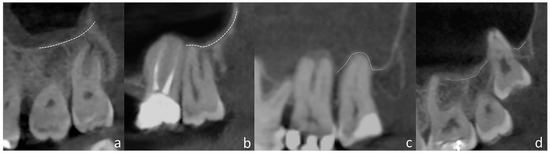

2.2. Image Acquisition and Evaluation